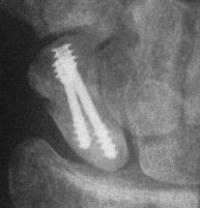

Case 5. Another,same bidirectional technique. Here, I ran the second screw too close to the first, and may have flattened the leading threads - not

ideal. The preop status:

Click for larger image

With intercalated iliac bone graft...

and healing.